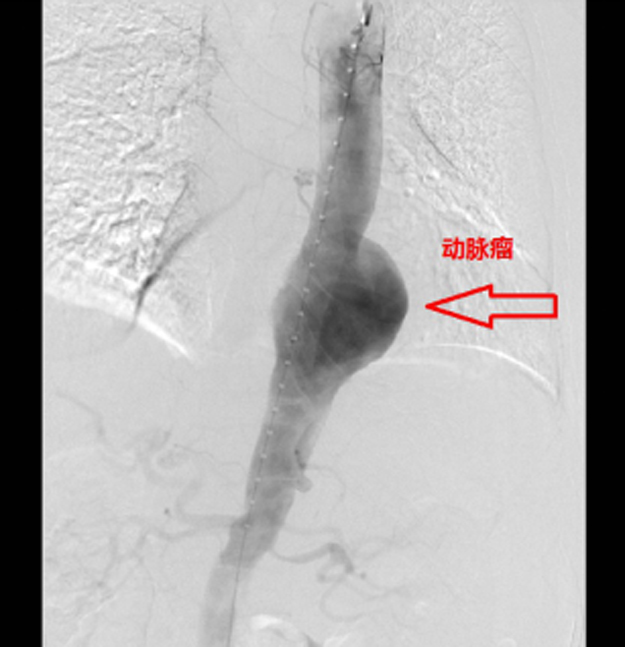

近日,梧州市工人医院心血管内科成功为一名主动脉瘤破裂出血的危急老人完成急诊主动脉覆膜支架腔内隔绝术,目前患者经过抢救,正在接受后续治疗。

家住广东封开的林老伯,今年70岁,因突然觉得胸腹部剧痛、难以忍受,遂到市工人医院急诊科就诊。经检查,医生发现林老伯主动脉瘤破裂出血,病情十分凶险!目前,抢救此类病人,最快速有效的方法是立即实行介入手术,通过支架把主动脉破裂口封闭,防止继续出血。

当天晚上,医院心血管内科高乐副主任医师在得知林老伯病情后,当机立断告知林老伯家属相关病情,并通知科主任黄达军主任医师及何国欢副主任医师及时到场做好手术准备。经过近2个小时的手术治疗,医生们终于将支架植入林老伯的主动脉并顺利封闭破裂口,成功抢救了命悬一线的林老伯。目前,林老伯病情渐稳,将继续住院行后续治疗。

(术后,林老伯体内巨大的动脉瘤已消失,破裂口被封闭)人体“不定时炸弹”——主动脉瘤